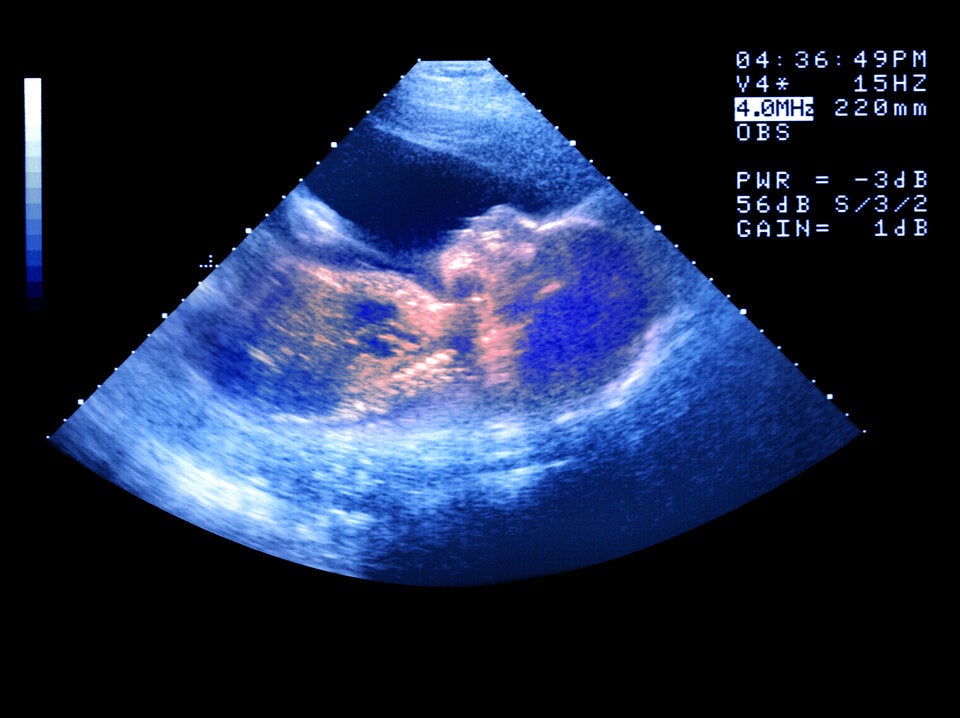

Stellen Sie sich vor, Sie hätten nicht zwei, sondern drei Eltern. Dieser medizinischer Durchbruch ist keine Science-Fiction-Premisse, sondern Realität für acht Babys, die in Großbritannien zur Welt gekommen sind.

Acht Kinder, geboren in Großbritannien, teilen sich ein seltenes genetisches Merkmal: Ihr Erbgut stammt nicht nur von Mutter und Vater, sondern zu einem kleinen Teil auch von einer dritten Person. Möglich wurde das durch eine experimentelle Technik, die helfen soll, schwere genetische Krankheiten zu verhindern.